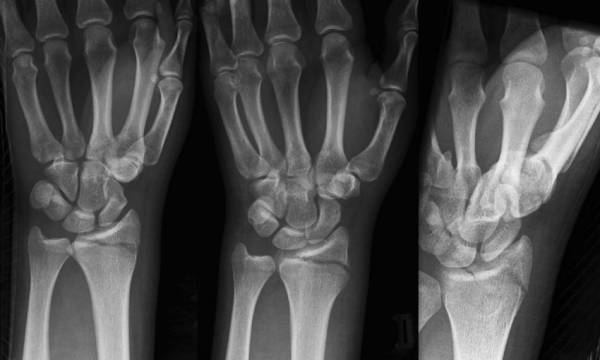

Colles骨折

桡骨远端伸直型骨折,远折端向桡背侧移位。是关节外骨折,常伴有尺骨茎突骨折。

Smith骨折

桡骨远端屈曲型骨折,骨折远端向掌桡侧移位。

Barton骨折

桡骨远端关节内骨折,伴桡腕关节脱位。